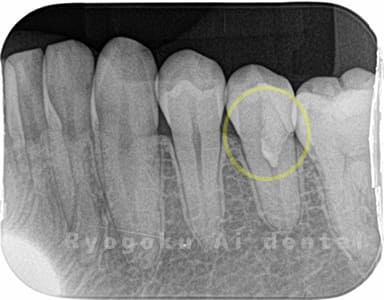

Case05

歯がしみるとのことで来院された患者様です。虫歯が神経まで及んでいましたが、神経を一部分カットする断髄治療を行いました。経過も良好です。

<リスク・副作用>

術後は痛み、腫れ、痺れなどの副作用が生じる場合があります。症状が再発する可能性があります。その場合は抜髄する必要があります。